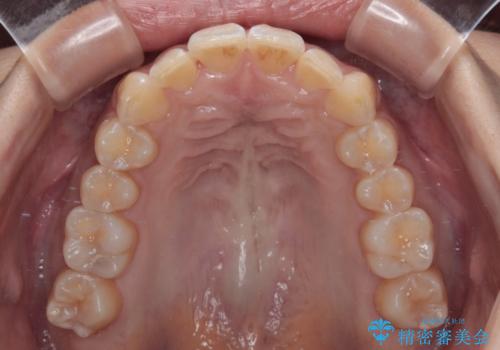

下顎前歯がデコボコしており、その影響で上顎前歯が前方に押し出されている状態でした。

上下左右の親知らずを抜歯し、上下ともに歯列を後方と側方に拡大し、口元を突出させることなくデコボコを解消することとしました。

前歯の形が台形であり、歯列が整ったところでブラックトライアングルが目立つ仕上がりとなったため、IPR(歯と歯の間を削る処置)によって歯の形態を修正し、隙間の目立たない歯列に仕上げることができました。